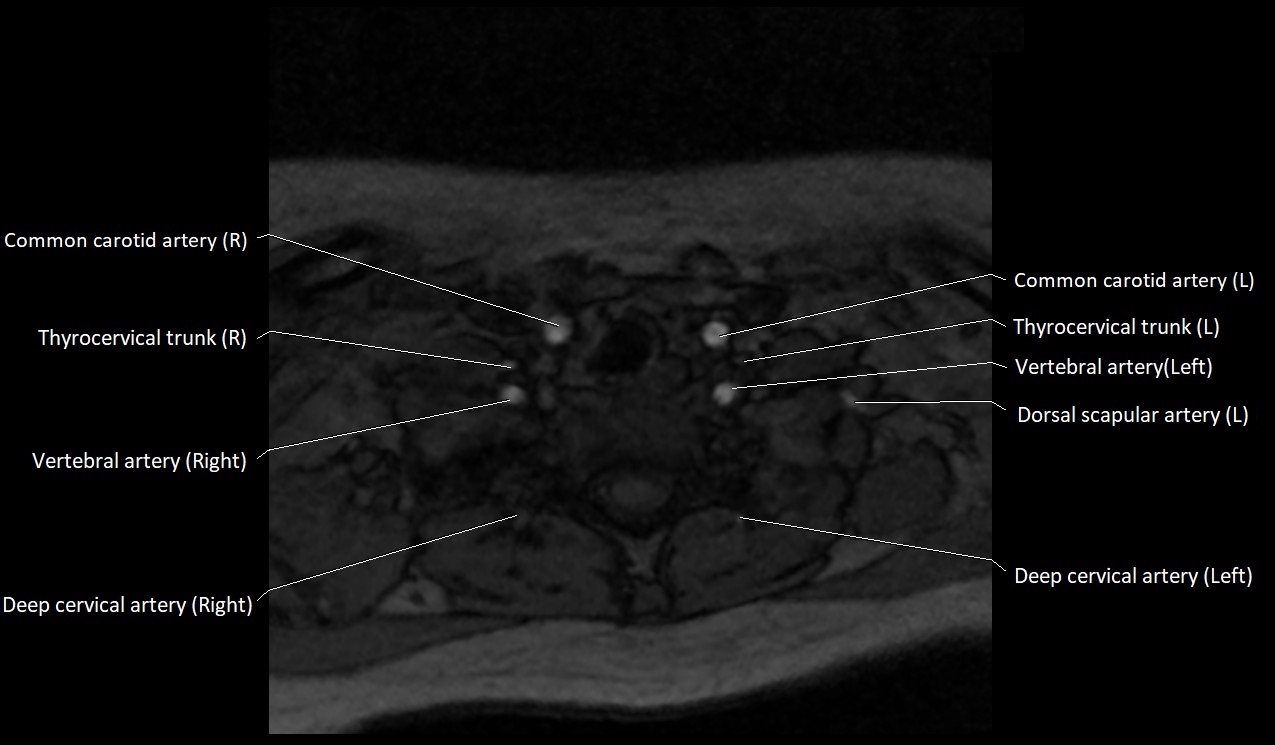

MRI Appearance:

• T1-Weighted Images:

• Appears as a tubular, hypointense (dark) structure relative to muscle

• May show flow void if the blood flow is fast

• T2-Weighted Images:

• Typically hypointense or isointense to muscle, but can be hyperintense if slow flow or stasis is present

MRI images

image